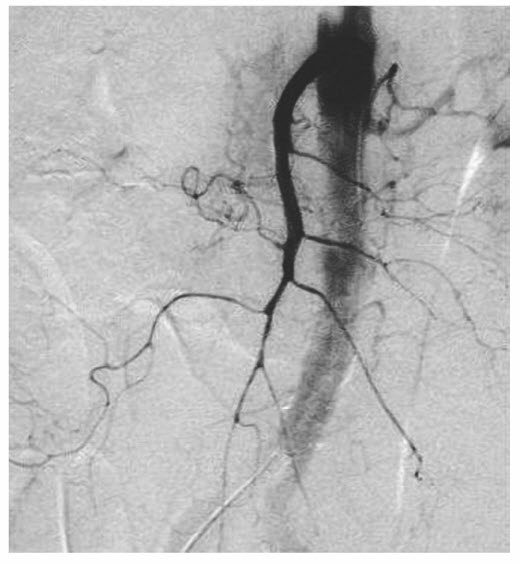

The treatment of nonocclusive mesenteric ischemia is primarily pharmacologic with selective mesenteric arterial catheterization followed by infusion of vasodilatory agents, such as tolazoline or papaverine. Once the diagnosis is made on the mesenteric arteriography (Fig. below), intra-arterial papaverine is given at a dose of 30 to 60 mg/h. This must be coupled with the cessation of other vasoconstricting agents.

Mesenteric arteriogram showing non-occlusive mesenteric ischemia as evidenced by diffuse spasm of i ntestinal arcades with poor filling of intramural vessels.